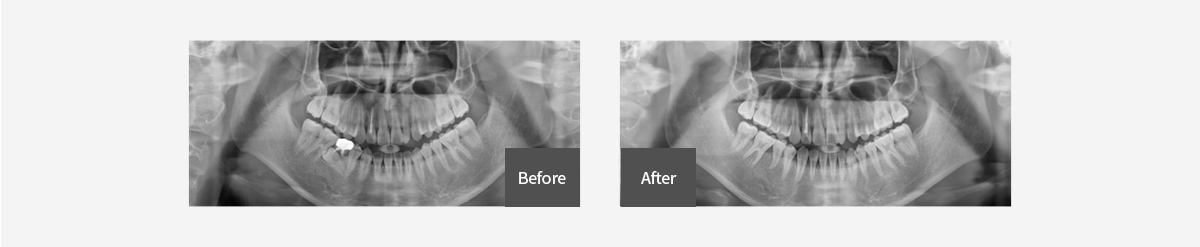

- 보철전교정

- 주로 성인에서 심한 충치나 치주질환으로 인해 빠진 치아를 임플란트로 해결이 필요한 경우가 많습니다

시간이 오래 지난 후 진행 시 주변치아의 이동으로 충분한 공간 확보가 어려운 경우 교정치료를 선행해 충분한 공간확보 후 보철이나 임플란트를 진행할 수 있습니다